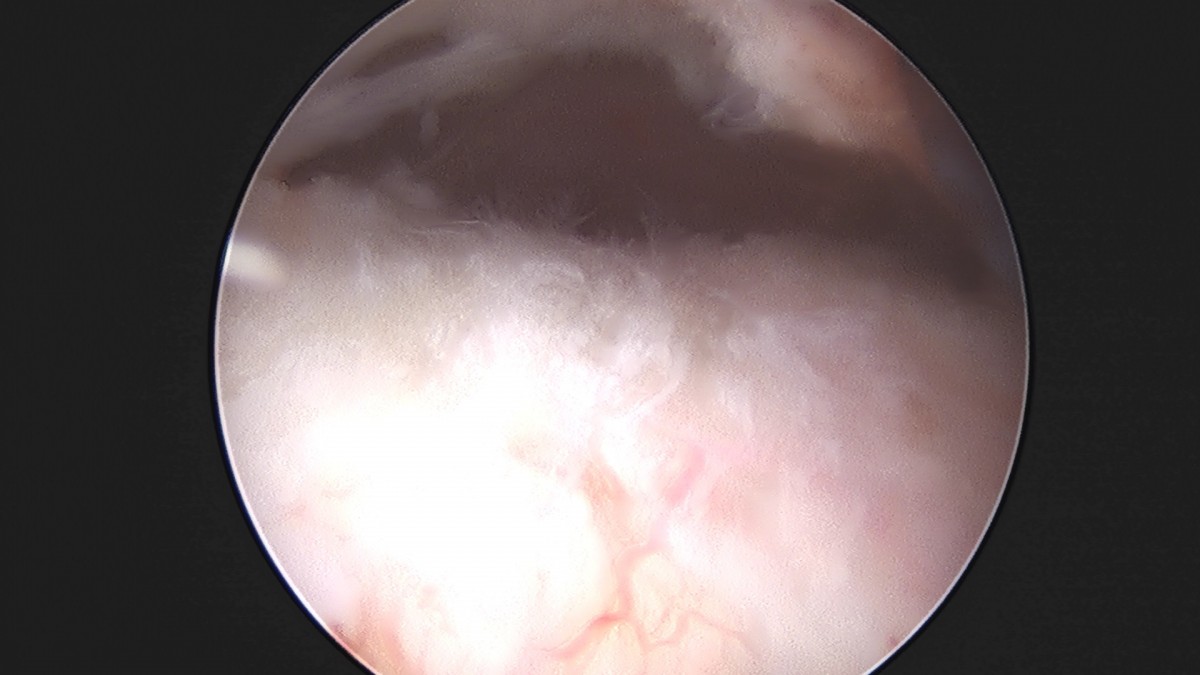

이재상원장님 어깨 견봉하 감압술 이승O 환자

작성자 최고관리자 댓글 0건 조회 806회 작성일 25-09-16 15:26